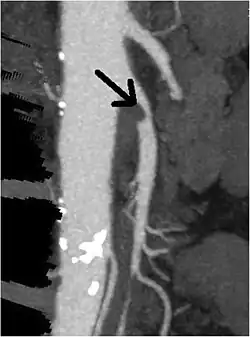

| CT angiogram demonstrating stenosis of the superior mesenteric artery. | |

Abdominal angina is diagnosed by identifying stenosis with imaging.[10] Since the symptoms of abdominal angina overlap with various other disorders, other causes of symptoms are ruled out as a part of the diagnostic process. Gastric ulcers, abdominal aortic aneurysms, and gastrointestinal cancers can have similar symptoms and can be ruled out by esophagogastroduodenoscopy, CT scans, or MR angiogram. Other differential diagnoses include GERD, dietary or food sensitivities, constipation, pancreatitis, abdominal abscess, appendicitis, irritable bowel syndrome, gastroenteritis, hepatitis, and inflammation of the gastrointestinal system.[11] Duplex ultrasound, MR angiography, angiography, and computed tomography angiography can be used to help confirm the diagnosis of abdominal angina.[3] Duplex ultrasound may be used to screen for abdominal angina but is not ideal for visualizing stenosis. Angiography, MR angiography, or CT angiography can be used to further visualize the celiac and mesenteric arteries.[12]